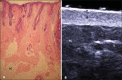

The present essay is aimed at getting the radiologist familiar with the basic histological skin structure, allowing for a better correlation with sonographic findings. A high-frequency (22 MHz) ultrasonography apparatus was utilized in the present study. The histological analysis was performed after the skin specimens fixation with formalin, inclusion in paraffin blocks and subsequent staining with hematoxylin-eosin. The authors present a literature review showing the relationship between sonographic and histological findings in normal cutaneous tissue, and discuss the technique for a better performance of the sonographic scan. High-frequency ultrasonography is an excellent tool for the diagnosis of different skin conditions. However, as this method is operator-dependent, it is crucial to understand the normal skin structure as well as the correlation between histological and sonographic findings.